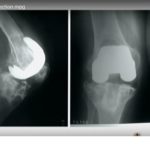

Prosthetic Joint Infection and Management

Courtesy: Hemanth Wakankar, Deenanath Mangeshkar Hospital, and Trivandrum Arthroplasty Course